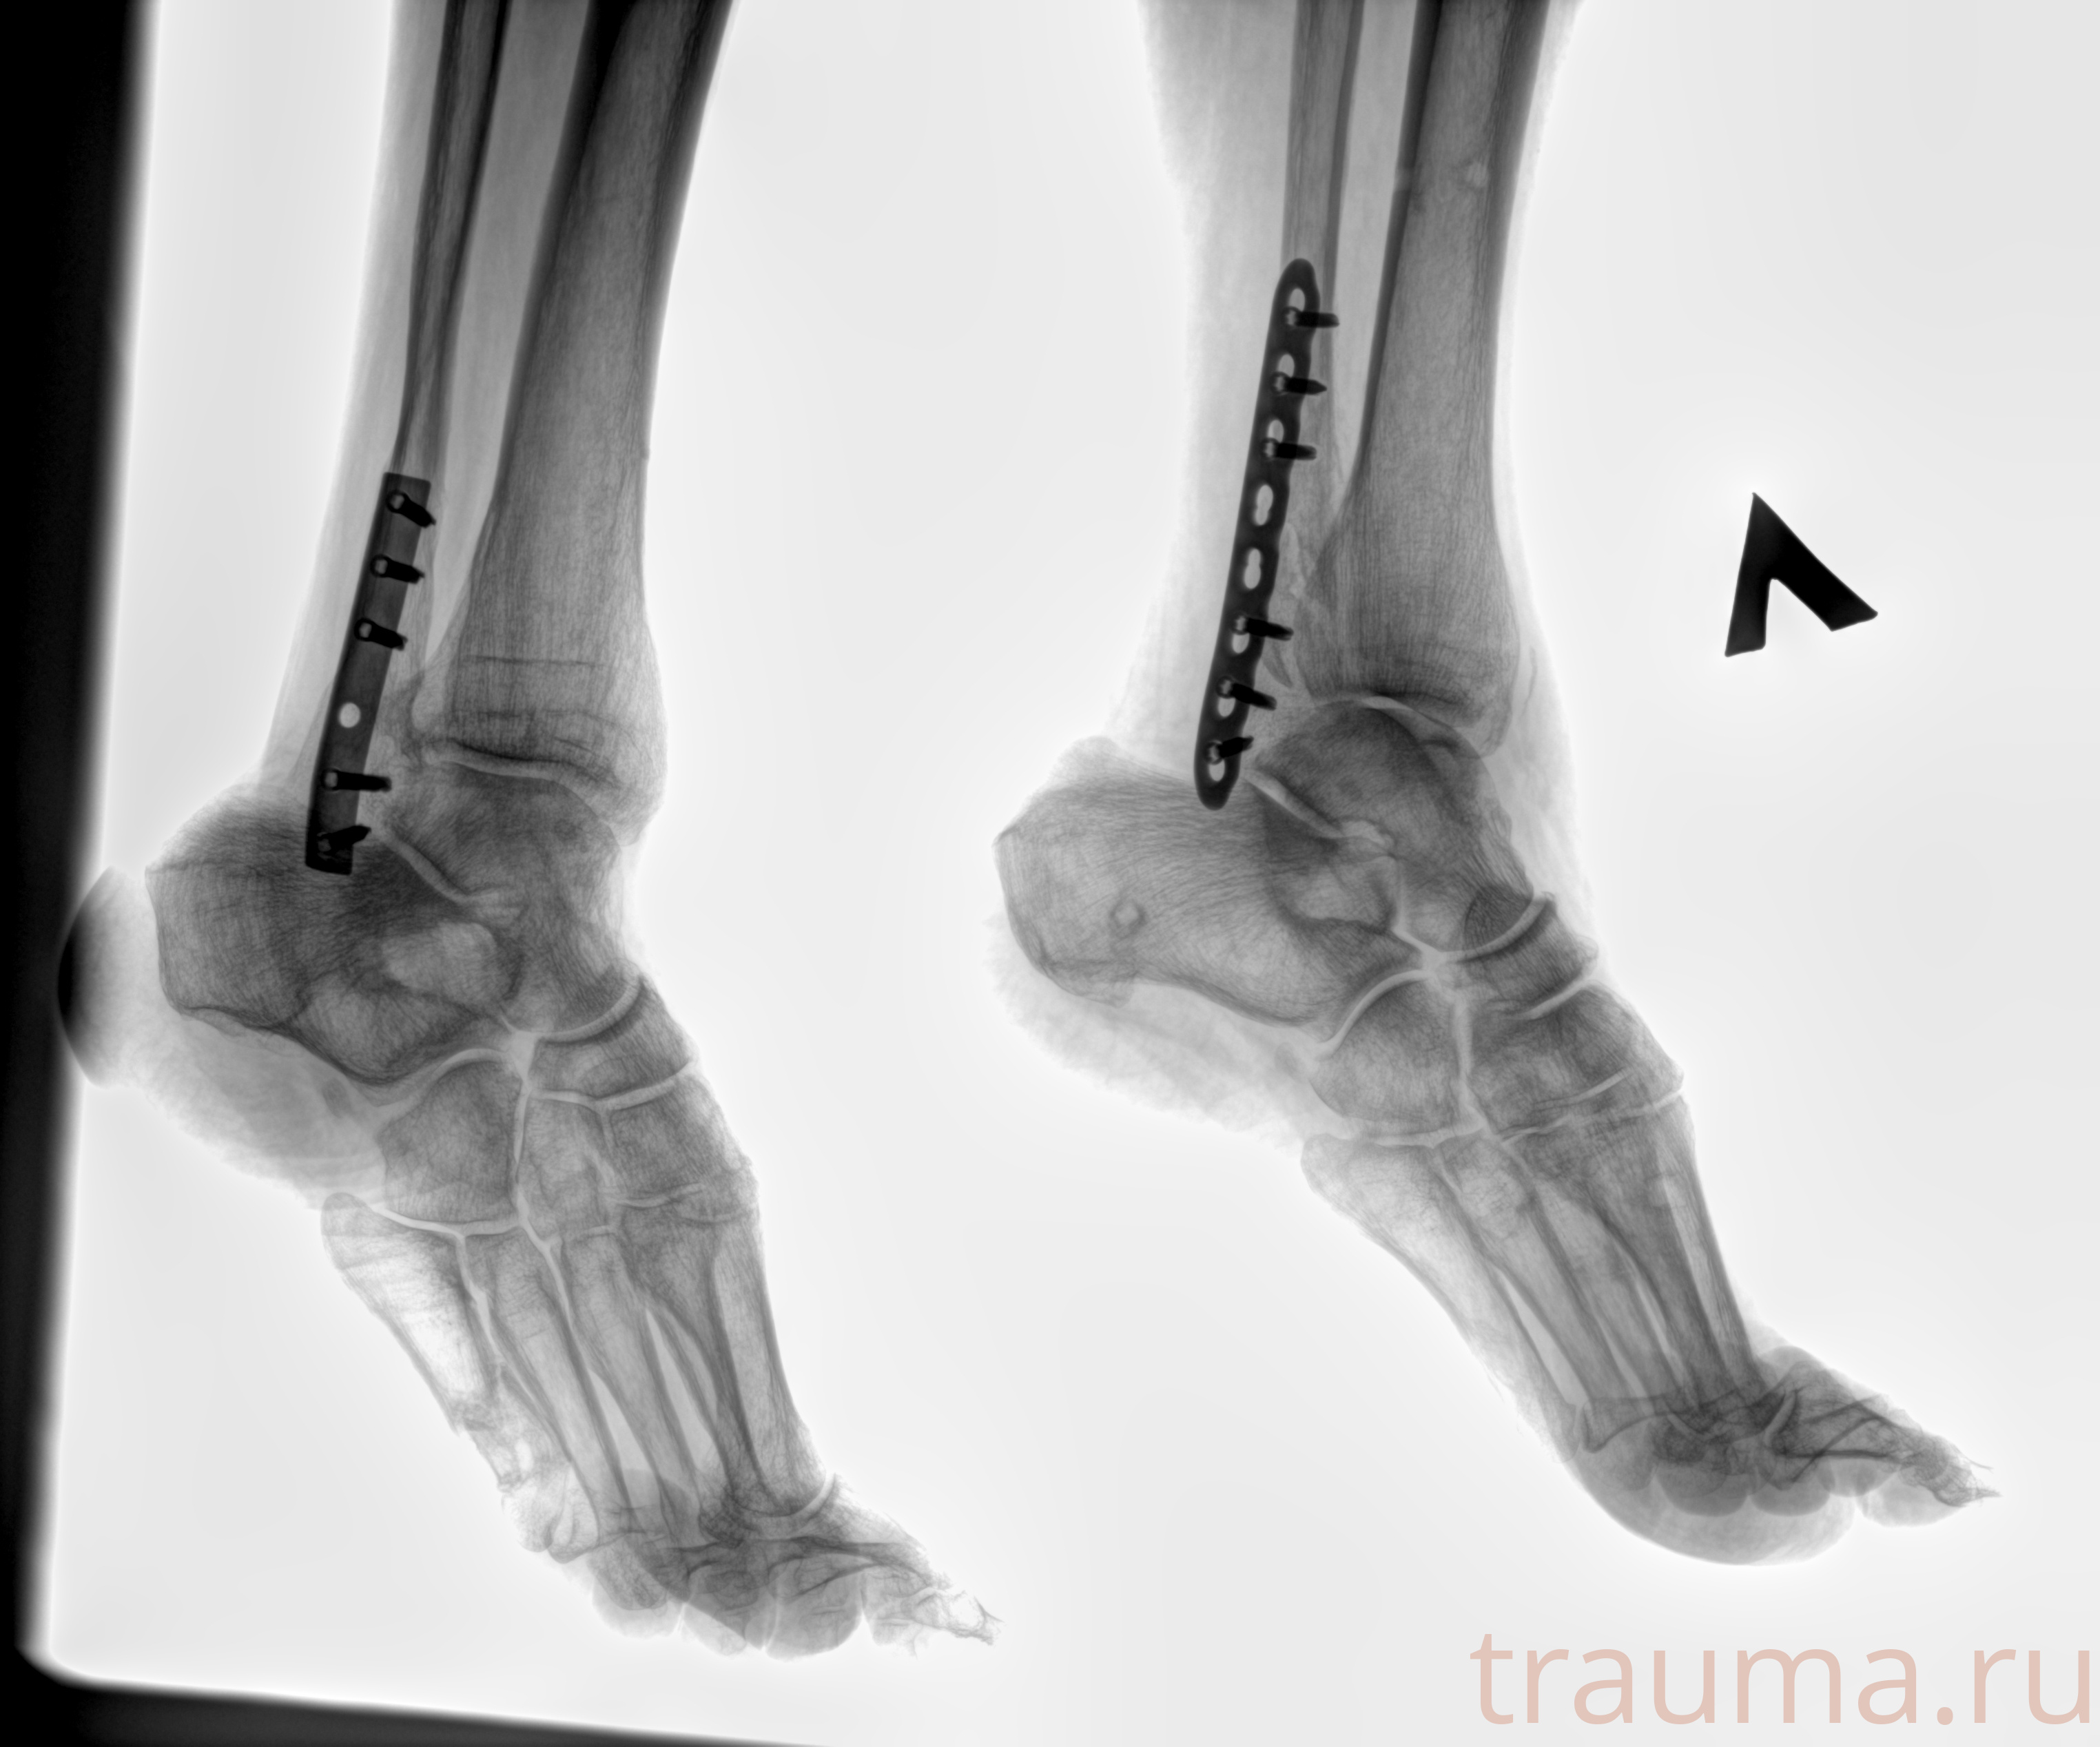

Рентген на дому: по вашему адресу приезжает врач-рентгенолог, травматолог-ортопед с мобильным рентгеновским аппаратом, проводит диагностику травмы или заболевания, делает необходимые рентгенограммы, дает рекомендации по дальнейшему лечению. Получить качественные снимки в домашних условиях возможно благодаря уникальной методике, разработанной МосРентген Центром для института  Склифосовского